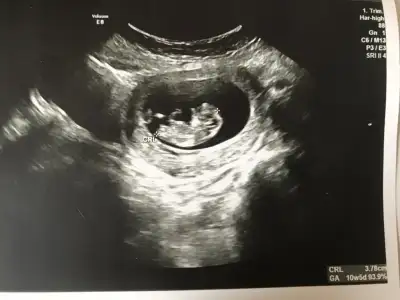

mrhaba lütfen yorumlarmisiniz sizce kızmı erkekmi bi arkadas icin soruyorum

Sevgili İkra,

Yorumlarsan çok sevinirim. ☺️❤️